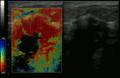

The two most commonly used screening methods, physical examination of the breasts by a healthcare provider and mammography, can offer an approximate likelihood that a lump is cancer, and may also detect some other lesions, such as a simple cyst.[93] When these examinations are inconclusive, a healthcare provider can remove a sample of the fluid in the lump for microscopic analysis (a procedure known as fine needle aspiration, or fine needle aspiration and cytology, FNAC) to help establish the diagnosis. A needle aspiration can be performed in a healthcare provider's office or clinic. A local anesthetic may be used to numb the breast tissue to prevent pain during the procedure, but may not be necessary if the lump isn't beneath the skin. A finding of clear fluid makes the lump highly unlikely to be cancerous, but bloody fluid may be sent off for inspection under a microscope for cancerous cells. Together, physical examination of the breasts, mammography, and FNAC can be used to diagnose breast cancer with a good degree of accuracy.

Other options for biopsy include a core biopsy or vacuum-assisted breast biopsy,[94] which are procedures in which a section of the breast lump is removed; or an excisional biopsy, in which the entire lump is removed. Very often the results of physical examination by a healthcare provider, mammography, and additional tests that may be performed in special circumstances (such as imaging by ultrasound or MRI) are sufficient to warrant excisional biopsy as the definitive diagnostic and primary treatment method.[95]